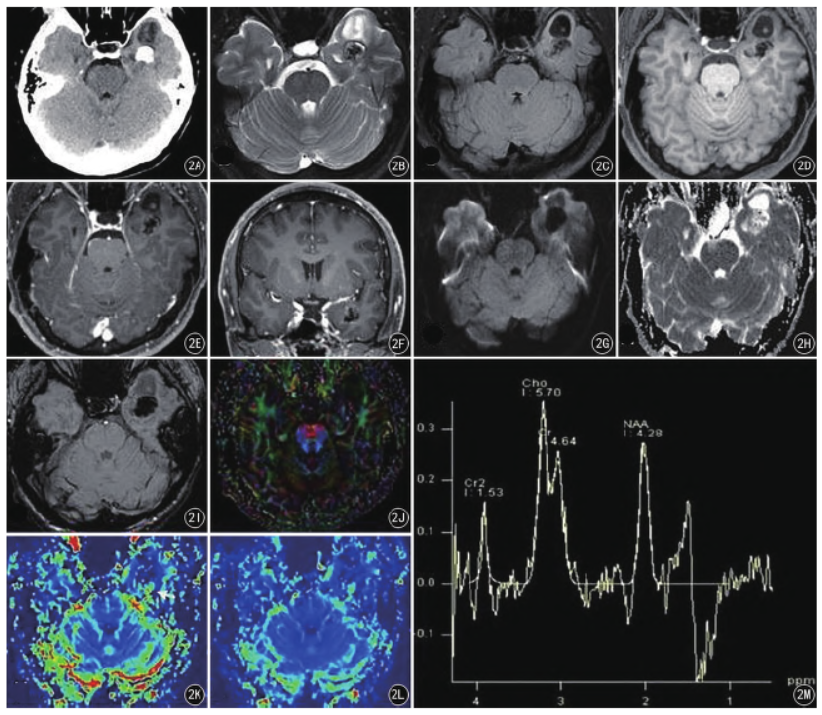

病例3,男,26 岁,发现左侧颞叶占位1 年,偶发抽搐。左颞叶肿块,轴位最大层面约1.7 cm × 3.7 cm,T1WI 为混杂低信号,T2WI 见“椒盐征”,内见囊变及钙化,增强后边缘轻度强化,周围脑组织稍肿胀,左侧脑室颞角受压;无扩散受限;DTI 示白质纤维束中断;SWI 见片结状、条状低信号;MRS 示NAA 峰略显降低,Cho 峰稍升高,Cho /NAA 比值约1.3;PWI 示病灶边缘点条状CBF、CBV 升高。CT 示病灶内明显“砂砾状”、结节状钙化,增强后后边缘强化( 图2) 。

图2A ~ M 病例3 患者图像,左侧颞叶PLNTY,轴位CT 平扫及MRI 多模态影像表现。轴位CT 平扫( A) 示病灶内结节状钙化,轴位T2WI 见“椒盐征”( B) ,轴位FLAIR 呈中央低边缘高信号( C) ,轴位T1WI 呈混杂低信号( D) ,轴位及冠状位T1WI 增强后见边缘轻度强化( E、F) ,DWI及ADC 示扩散未见受限( G、H) ,SWI 见病灶内低信号( I) ,DTI 示局部白质纤维束中断( J) ,PWI 见CBV、CBF 增高( K、L) ,MRS 示Cho 峰值增高,NAA 峰值减低,Cho /NAA 倒置,比值约为1.3